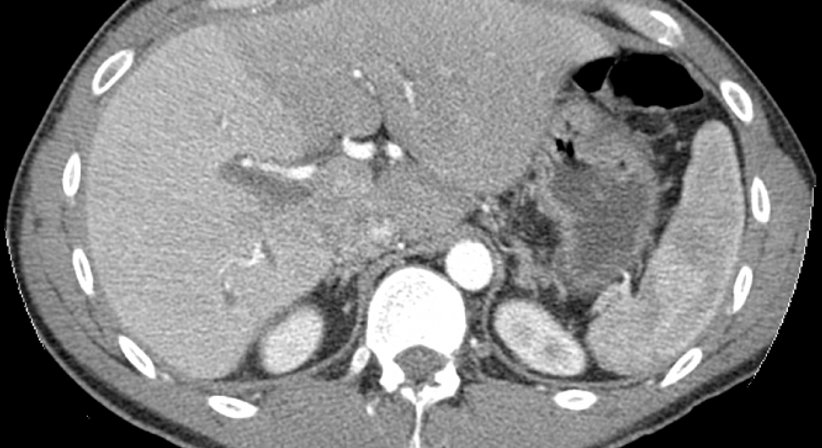

Die CT ist eine ausgezeichnete Methode zur Untersuchung und überlagerungsfreien Darstellung von Veränderungen im Körper.

Sie ist besonders zur Untersuchung der Lunge und des Bauchraumes geeignet.

Durch die jeweiligen Abschwächungen der Strahlenenergie können mittels Computer Schnittbilder der untersuchten Region errechnet werden. Durch die Gabe von Kontrastmittel über die Vene kann die Aussagekraft der Untersuchung noch gesteigert werden. Kontrastmittel sind meist jodhältige Substanzen die sich in den verschiedenen Organen wie Leber, Nieren, Milz etc. anreichern. Durch Störungen oder Änderungen der Kontrastaufnahme ergeben sich Bilder, die Rückschlüsse auf die Charakteristik von Veränderungen zulassen.